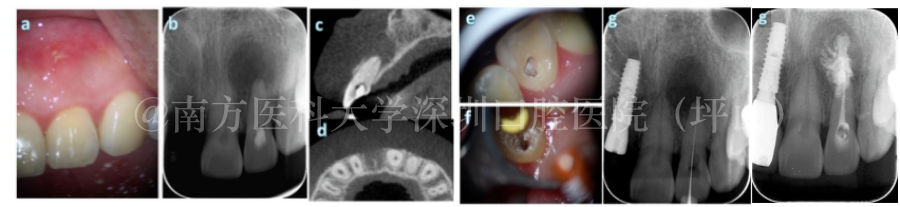

1 活髓保存治疗 活髓切断术+断冠再接 八岁男孩牙外伤,导致牙冠折断,里面的牙髓露出来了。由于恒牙的牙根并没有发育好,医生还是要尽量尝试保留健康的牙髓,促进牙根继续发育,将断掉的牙冠再粘回去,延长牙齿的使用寿命。 2 根管治疗 当出现牙髓组织不能保留、牙髓出现炎症且炎症不能恢复、牙髓坏死、细菌已从牙根的根管侵入到牙槽骨进而造成根尖周炎等情况时,需要进行根管治疗。 根管治疗目前是国际上公认的治疗牙髓病和根尖周疾病的最有效的方法,成功率一般在85%~90%。由于根管系统和髓腔的解剖结构的复杂性和多样性、微生物变种及毒力改变、医疗器械或医生临床技能的差异等因素,根管治疗仍有一定的失败率。 医生建议,根管治疗后,最好戴上牙冠(或嵌体)来保护牙齿,提高牙齿远期留存率,同时也更加美观。 3 牙髓再生治疗(血运重建术) 对于一些牙根没有发育好的牙齿,我们可以尝试牙髓血运重建术,就是提取血液中的干细胞,进入到牙齿内部增殖、分化,形成类似于牙髓组织的结构。 这样做了治疗以后,牙齿还有牙髓组织,还有血液供应,牙根还能够继续发育。 血运重建术

8岁男孩复杂冠根折